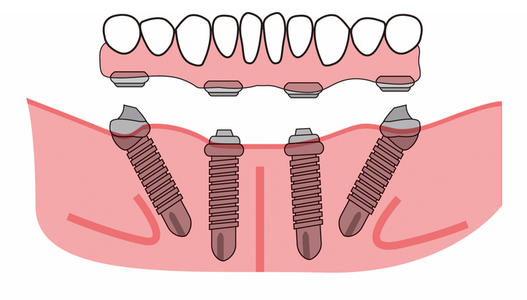

All-on-4种植牙运用微创种植牙技术,24小时内即可戴上临时牙,戴牙后2小时便可恢复患者咀嚼功能,无需传统种植的漫长等待。随着种植修复技术的发展,All-on-4技术的适用范围还在不断扩大,造福更多的半口无牙和全口无牙的患者。

相对传统的全口、半口种植修复,All-on-4技术仅需植入传统种植牙一般的植体,大大降低手术时间和创伤。 》》》相关阅读:在廊坊,种植牙能用多长时间?

所有全口、半口无牙患者都是All-on-4的适应人群,过去全口或半口等牙列缺失的患者往往要接受植骨手术,承担多次手术和较长的愈合期,All-on-4技术真正做到即使在骨量严重萎缩的情况下,也可利用斜行植体等技术,避免植骨手术。

3.半口仅需4-6颗种植体

All-on-4结合倾斜植体和即刻负重等外科与修复方面的创新,实现在手术当日即刻负重,只需4个植体就可做半口固定义齿修复。

All-on-4植牙修复方案的出现,一次解决上排或下排牙齿的重建工作。装上假牙以后,当天晚上就能正常进食,解决每天配戴活动假牙的麻烦。 》》》相关阅读:在廊坊,种植牙的类型有哪几种?